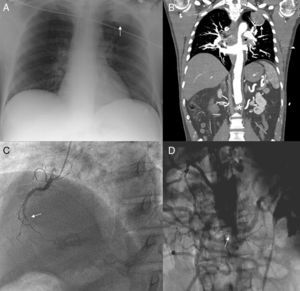

Caso clínicoVarón de 57 años de edad, sin factores de riesgo cardiovascular, salvo fumador de 30 cigarrillos/día, y sin antecedentes de cardiopatía isquémica ni EAP, que ingresa por dolor centrotorácico de características isquémicas asociado a cortejo vegetativo de una hora de evolución. Al ingreso se evidenció en el electrocardiograma elevación del ST en la cara inferior, hipocinesia inferior en la ecocardiografía y una masa en el lóbulo superior izquierdo en la radiografía de tórax (fig. 1A). Debido a la presencia hipertensión arterial severa de difícil control y a la ausencia de pulsos femorales, asociada a dolor abdominal difuso, se decidió la realización de una tomografía computarizada (TC) toracoabdominal con el fin de descartar la existencia de disección de aorta. En esta se confirmó la presencia de una masa pulmonar, sospechosa de neoplasia, y la existencia de una oclusión de la aorta abdominal a nivel infrarrenal (fig. 1B) sin datos de disección. Ante estos hallazgos, y ante la dificultad en el control de la presión arterial, se decidió la realización de un cateterismo cardiaco urgente por vía radial. En este se evidenció la oclusión de la arteria coronaria derecha (fig. 1C), que se recanalizó con el implante de 2 stents convencionales, y la oclusión de la aorta abdominal a nivel infrarrenal con abundante circulación colateral (fig. 1D).

A) Radiografía de tórax en posteroanterior evidenciando una masa a nivel del lóbulo superior izquierdo (flecha). B) Tomografía computarizada toracoabdominal, corte coronal, donde se evidencian la masa pulmonar (flecha) y la oclusión de la aorta a nivel abdominal (asterisco). C) Coronariografía (oblicua anterior derecha) en la que se evidencia oclusión de la coronaria derecha a nivel de tercio medio (flecha). D) Aortografía abdominal (anteroposterior) donde se evidencia oclusión a nivel de la aorta abdominal (flecha) con abundante circulación colateral.